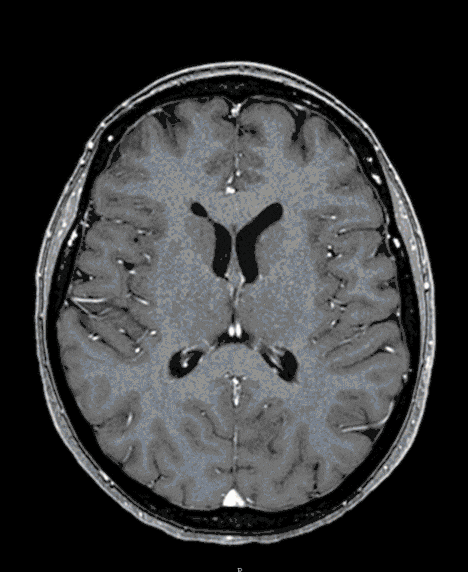

Skull Base Meningioma

Skull-based meningiomas are mostly benign tumors that can grow considerably due to their nature and slow growth. They threaten the function of the brain and its exiting nerves (cranial nerves of the brain stem).